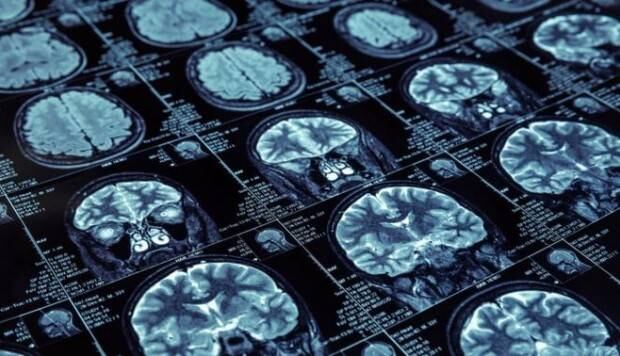

¿Cómo hicieron esto? Mediante una resonancia magnética midieron el grosor de los LTM de cada uno de ellos, descubriendo que esta parte se atrofiaba mientras más tiempo las personas pasaban sentadas. Esto sin importar cuánta actividad física hagan. Mientras más tiempo lleven una vida sedentaria, peor será el resultado.